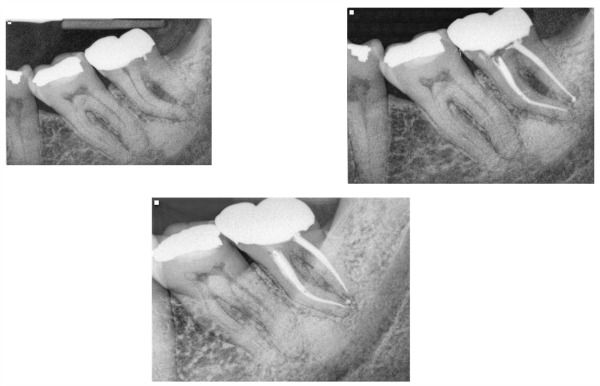

Tips to Finding the MB2 in Maxillary Molars

Endodontics

May 1, 2013

3 min read